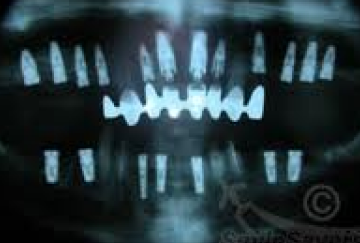

It takes 5 to 10 years before an implant dentist knows how successful his/her treatment is. Differences in technique, implant design and follow-up (regular hygienist sessions, regular examinations and Xrays by clinicians who know their field)… have a massive impact on long-term appearance and function.

The techniques we employ to ensure optimal implant position and long term health of peri-implant tissues (bone and gum) have changed drastically over time. We now know that if an implant is placed too close to the bone surface that this will frequently cause early recession and metal parts becoming exposed. The implant may still be good for chewing but if exposed metal shows when you smile, it’s not a good look.

The design of the implants and the parts we attach to them to support the new teeth have evolved over the last 4 decades. Improved surface treatment of the titanium means that the bone in the jaw attaches more readily to the titanium these days…thread design evolution allows newly fitted implants to fit more firmly in the bone from day 1 meaning that immediate teeth/teeth in a day/early loading are now possible where they weren’t 20 years ago. Patients get their teeth sooner these days – in the 90s they would wait 12+months for implants to be ready to accept the new teeth